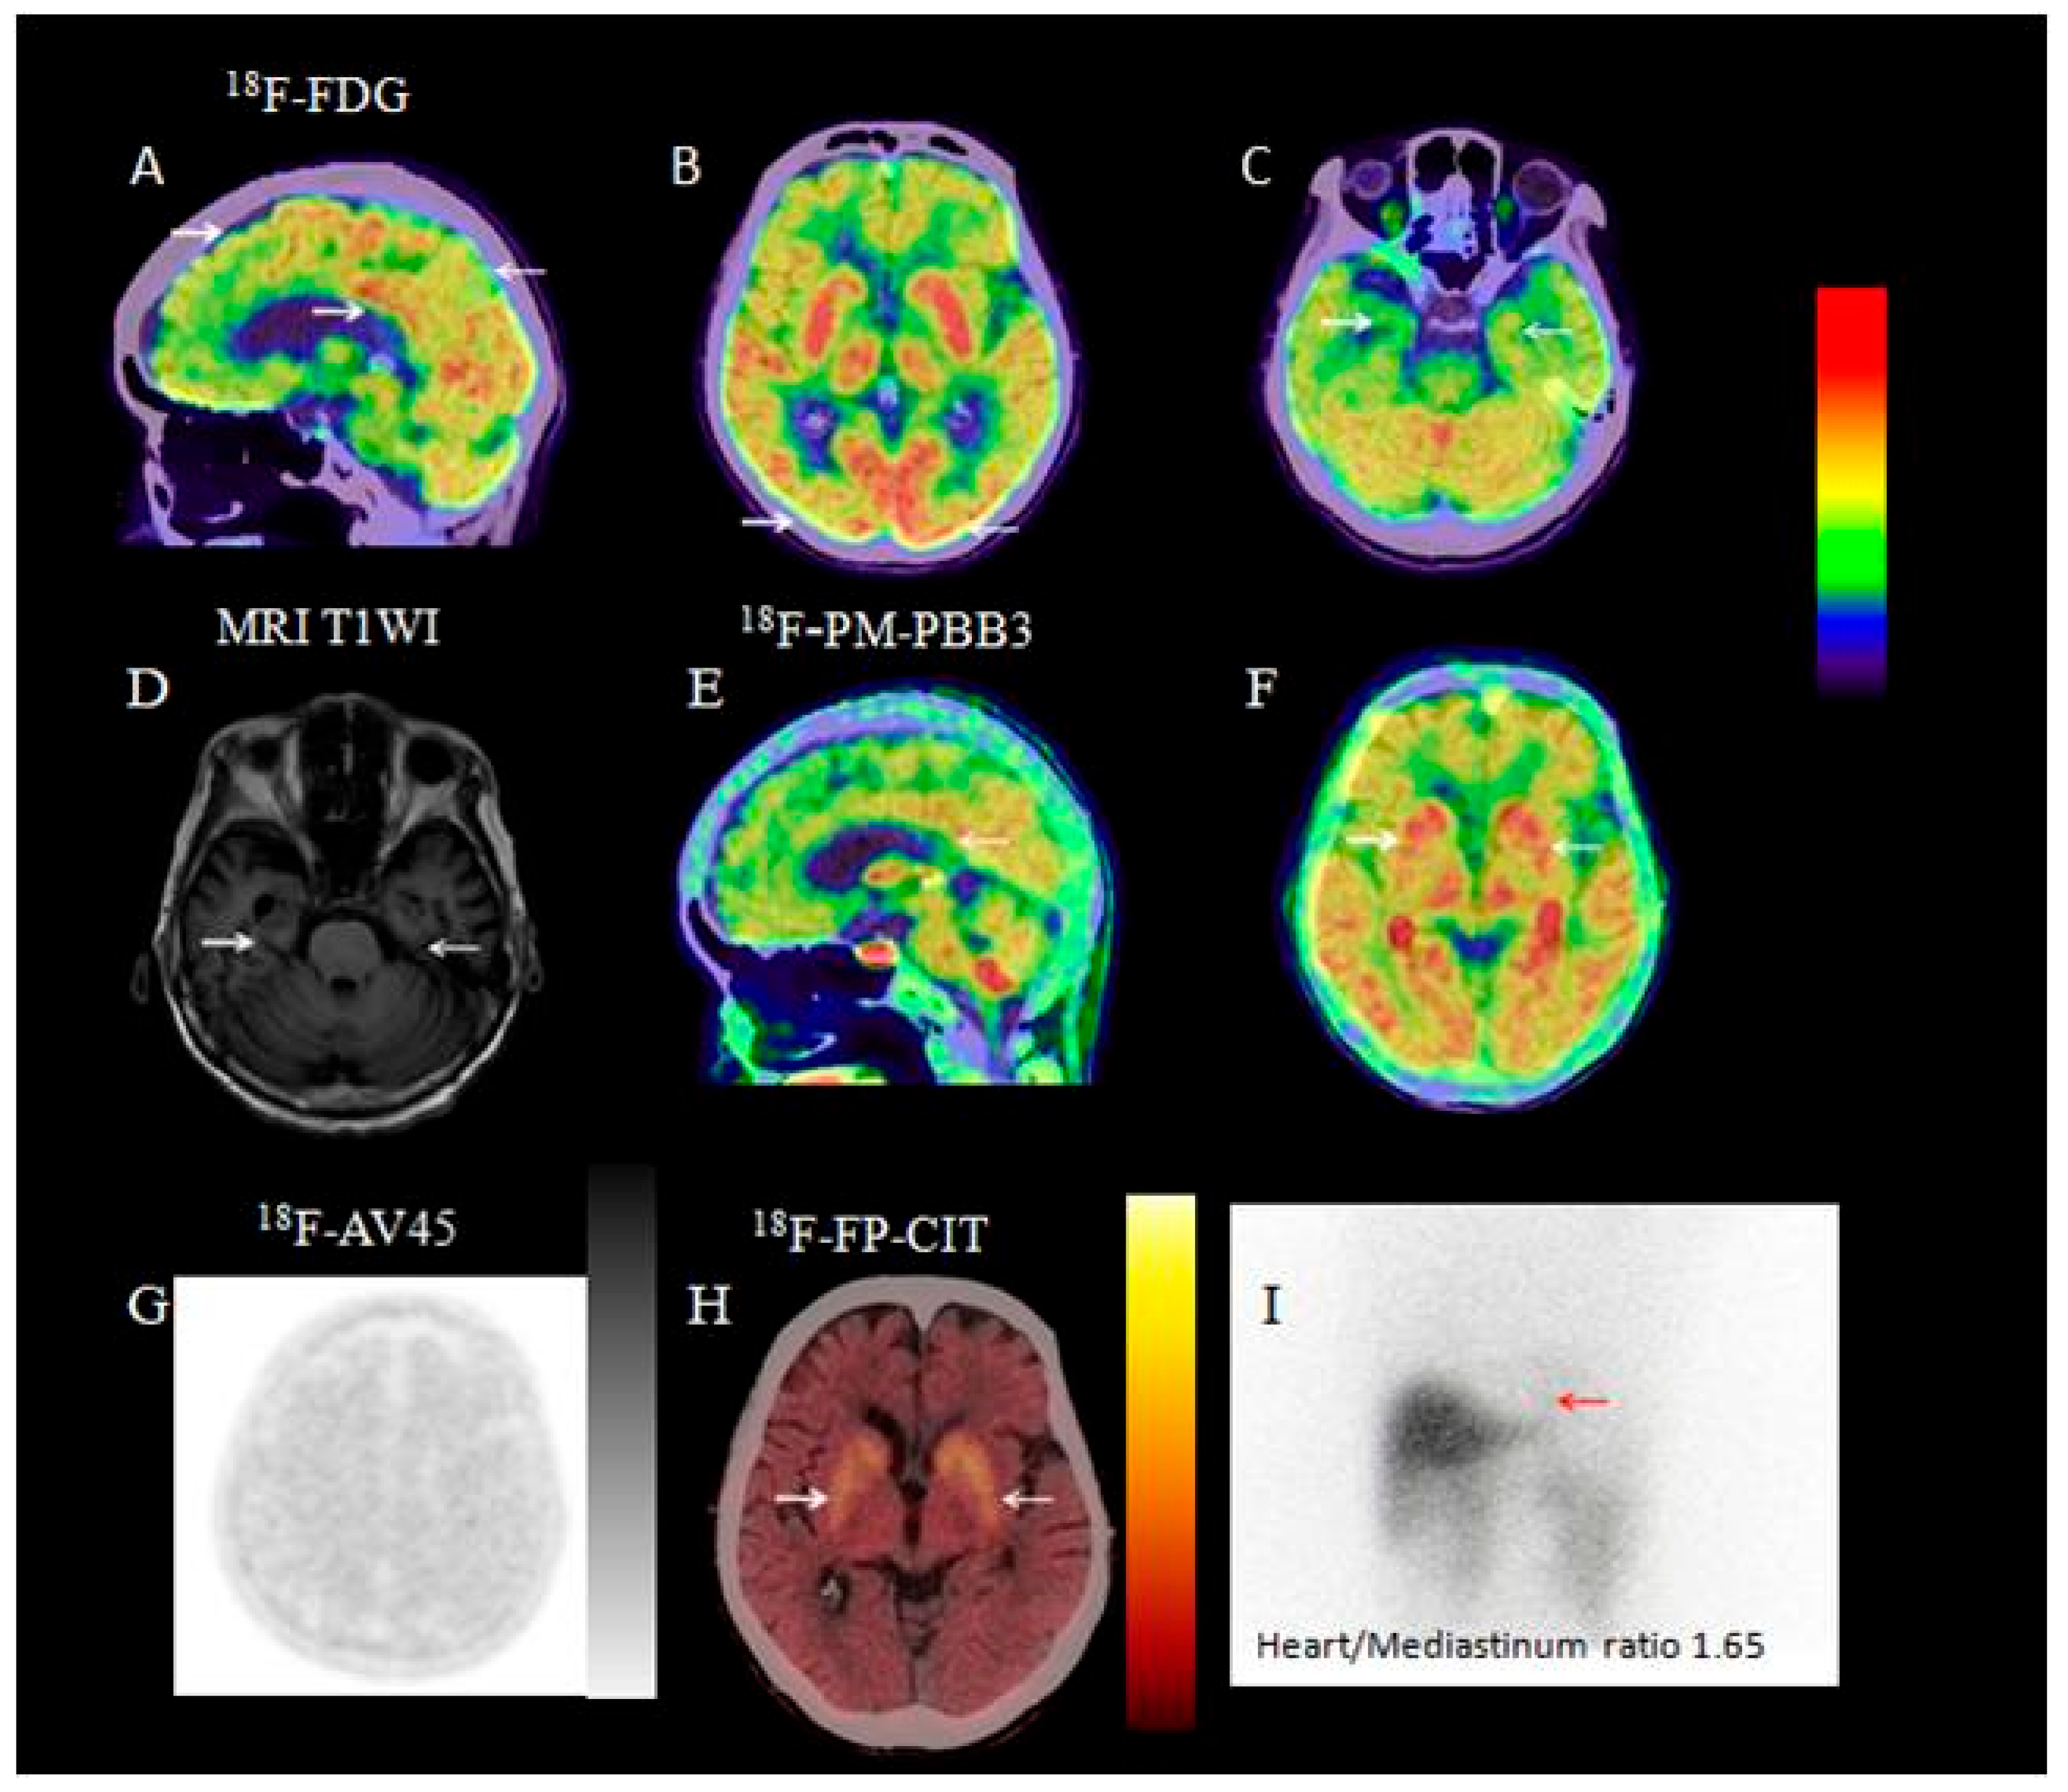

3.2.7. Visual Analysis of 131I-MIBG SPECT

3.2.8. Visual Analysis of 18F-PM-PBB3 PET/CT